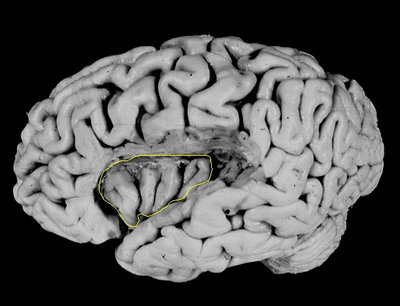

Figure 2: . The spinothalamic system projects to the outer layers of the spinal dorsal horn from whether projections exist via a thalamic relay nucleus (VMpo) to the posterior insular cortex. The somatosensory system located in the anterior parietal cortex. From: the digital anatomist project in the department of biological structure at the University of Washington